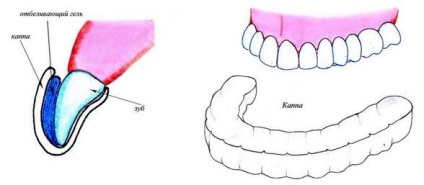

- Home. Ez magában foglalja a használata egy speciálisan kialakított tálca, amely figyelembe veszi az összes funkcióját a szájához. Ebben az esetben a fehérítő eljárás önmagában lehet tenni otthon, de még mindig van, hogy fogorvoshoz készülő fogvédő.

Fogak fehérítésére otthon keresztül mouthguards

Az ilyen típusú fehérítő nem ad ilyen gyors hatás, mint az előző, de a bónusz, hogy végezzen eljárások otthon. De először meg kell, hogy készítsen egy fogvédő, ami történik, több szakaszból áll:

- A klinika fogászati benyomások venni mind az alsó és felső állkapocs.

- Ennek alapján a benyomások a laboratóriumban azt szilikonból készült tálcát.

- Az orvos megpróbálja kappa beteg.

- Ha minden jól megy, a választott színtől alatti aktív gél.

- Fogorvos költ beteg utasítást, hogy hogyan végezze el fogfehérítés.

Fotó: fehérítés kappa

Fontos otthoni fogfehérítés tart egy-két hétig. Ezen eljárás során, egy speciális tálcát töltött fehérítő gél, amely után vannak elhelyezve a fogak éjjel, mivel a tevékenység a gél tart, körülbelül 10 órán át.